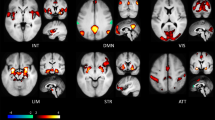

Mood profiles before and after treatment showed changes in the overall instability pattern (see Supplementary Table S.3.). To investigate how changes in the temporal structure affected the mood profile, the probability of moving between different mood states, we determined the probability transitions between three QIDS-SR score states (zero, mild and moderate levels), (see Materials and methods; Daily mood monitoring). At an individual patient level, our analysis revealed a general increase in the probability of observing patients with low QIDS-SR scores (<9) after treatment and a reduction in the probability of high QIDS-SR scores (⩾9). Individual patient analyses were possible given the appropriate monitoring before and after treatment, and the details of this approach (using a Markov chain analysis) and the results for each patient are reported in Figure 2 (and individual level data in Supplementary Table S.3.). Figure 2 shows the general patterns of changes in the long-term probabilities of QIDS-SR scores in each of the three states (zero, mild and moderate levels) before and after treatment per patient. This analysis showed that in 11 of 14 cases, there was an improvement in mood profiles with a decreased occurrence of high QIDS-SR scores (>9), and hence less time spent above the clinical cut-off for depressed mood. Further, 7 out of 14 patients had more zero QIDS-SR scores post-treatment, and hence had no reported mood dysfunction (see Figure 2).

Markov chain analysis of changes in QIDS-SR daily scores for individual participants pre- and post-treatment. Circle size represents the probability of a patient being in a certain mood state: red circles represent moderate levels of depression (QIDS-SR⩾9); orange circles represent mild levels of depression (QIDS-SR⩽9 and not equal to 0); green circles represent the absence of any depressive symptoms (QIDS-SR=0). For a given participant, this gives a picture of transition between states during their 28-day baseline phase (front triangle) which can be compared with their 28-day post-treatment phase (back triangle).